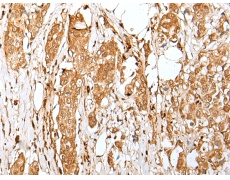

IHC positive control: |

Human tonsil and human breast cancer |

IHC Recommend dilution: |

30-150 |